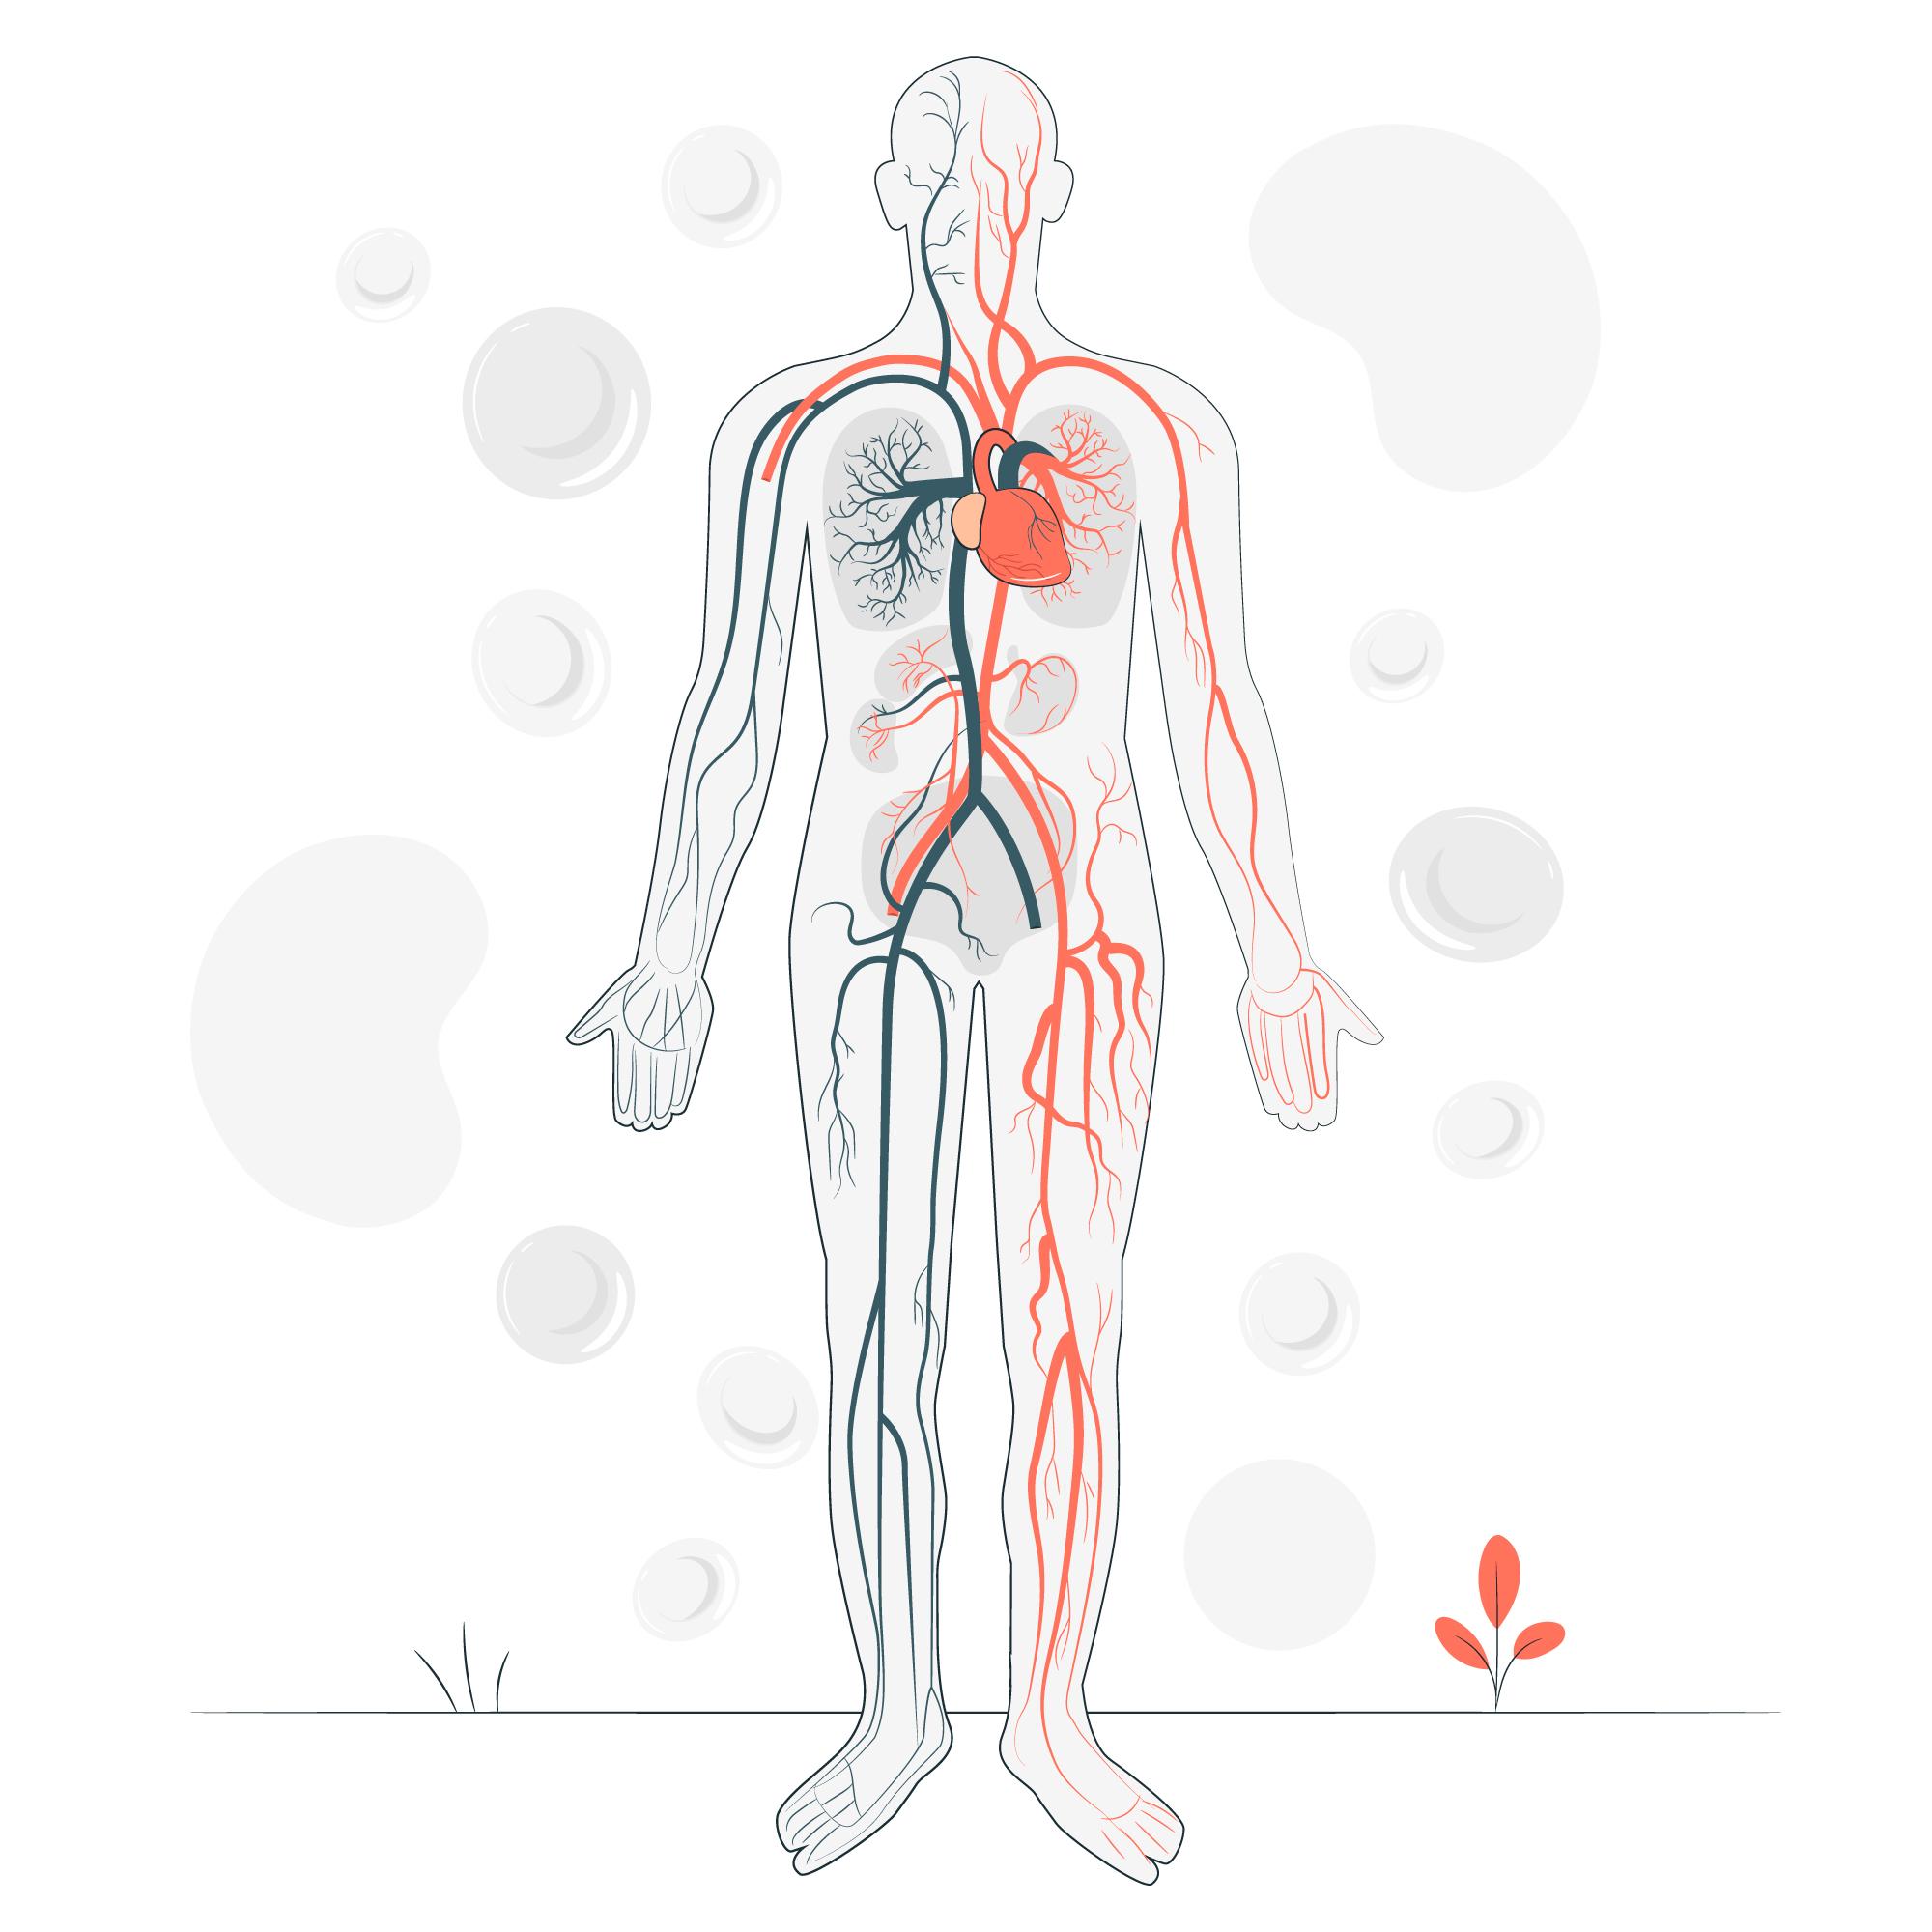

SN educated Pt/CG that High blood pressure (hypertension) is a common condition in which the long-term force of the blood against your artery walls is high enough that it may eventually cause health problems, such as heart disease. Blood pressure is determined both by the amount of blood your heart pumps and the amount of resistance to blood flow in your arteries. Generally, the hypertension is treated with exercises, salt restriction and medication.

SN educated patient/caregiver that heart failure, also called Congestive Heart Failure (CHF), means your heart does not pump blood as well as it should. This does not mean your heart has stopped working, but that it is not as strong as it used to be and fluid builds up in the lungs and other parts of your body. This can cause shortness of breath, swelling in the legs, feet, and stomach. Heart failure starts slowly and can get worse over time.

SN educated patient/caregiver about the heart is a muscle that pumps oxygen-rich blood to all parts of the body. When you have heart failure, the heart is not able to pump as well as it should. Blood and fluid may back up into the lungs (congestive heart failure), and some parts of the body don’t get enough oxygen-rich blood to work normally. These problems lead to the symptoms of heart failure. Follow a heart healthy diet. And make sure to limit the salt (sodium) in your diet. Salt causes your body to hold water. This makes your heart work harder as there is more fluid for the heart to pump. This makes that fluid builds up in the lungs and other parts of your body. This can cause shortness of breath, swelling in the legs, feet, and stomach. Heart failure starts slowly and can get worse over time.